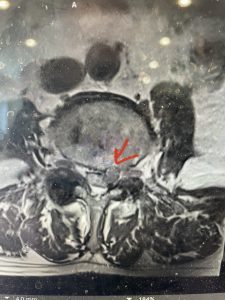

(Figs 5a): Sagittal (a) and axial (b) T2-weighted lumbar MRI demonstrating status post lumbar decompression and insitu fusion L2-5 now well decompressed (blue dash) with development of new (red arrow) severe stenosis and with superimposed right L1-2 disc herniation (blue arrow)

(Figs 5b)